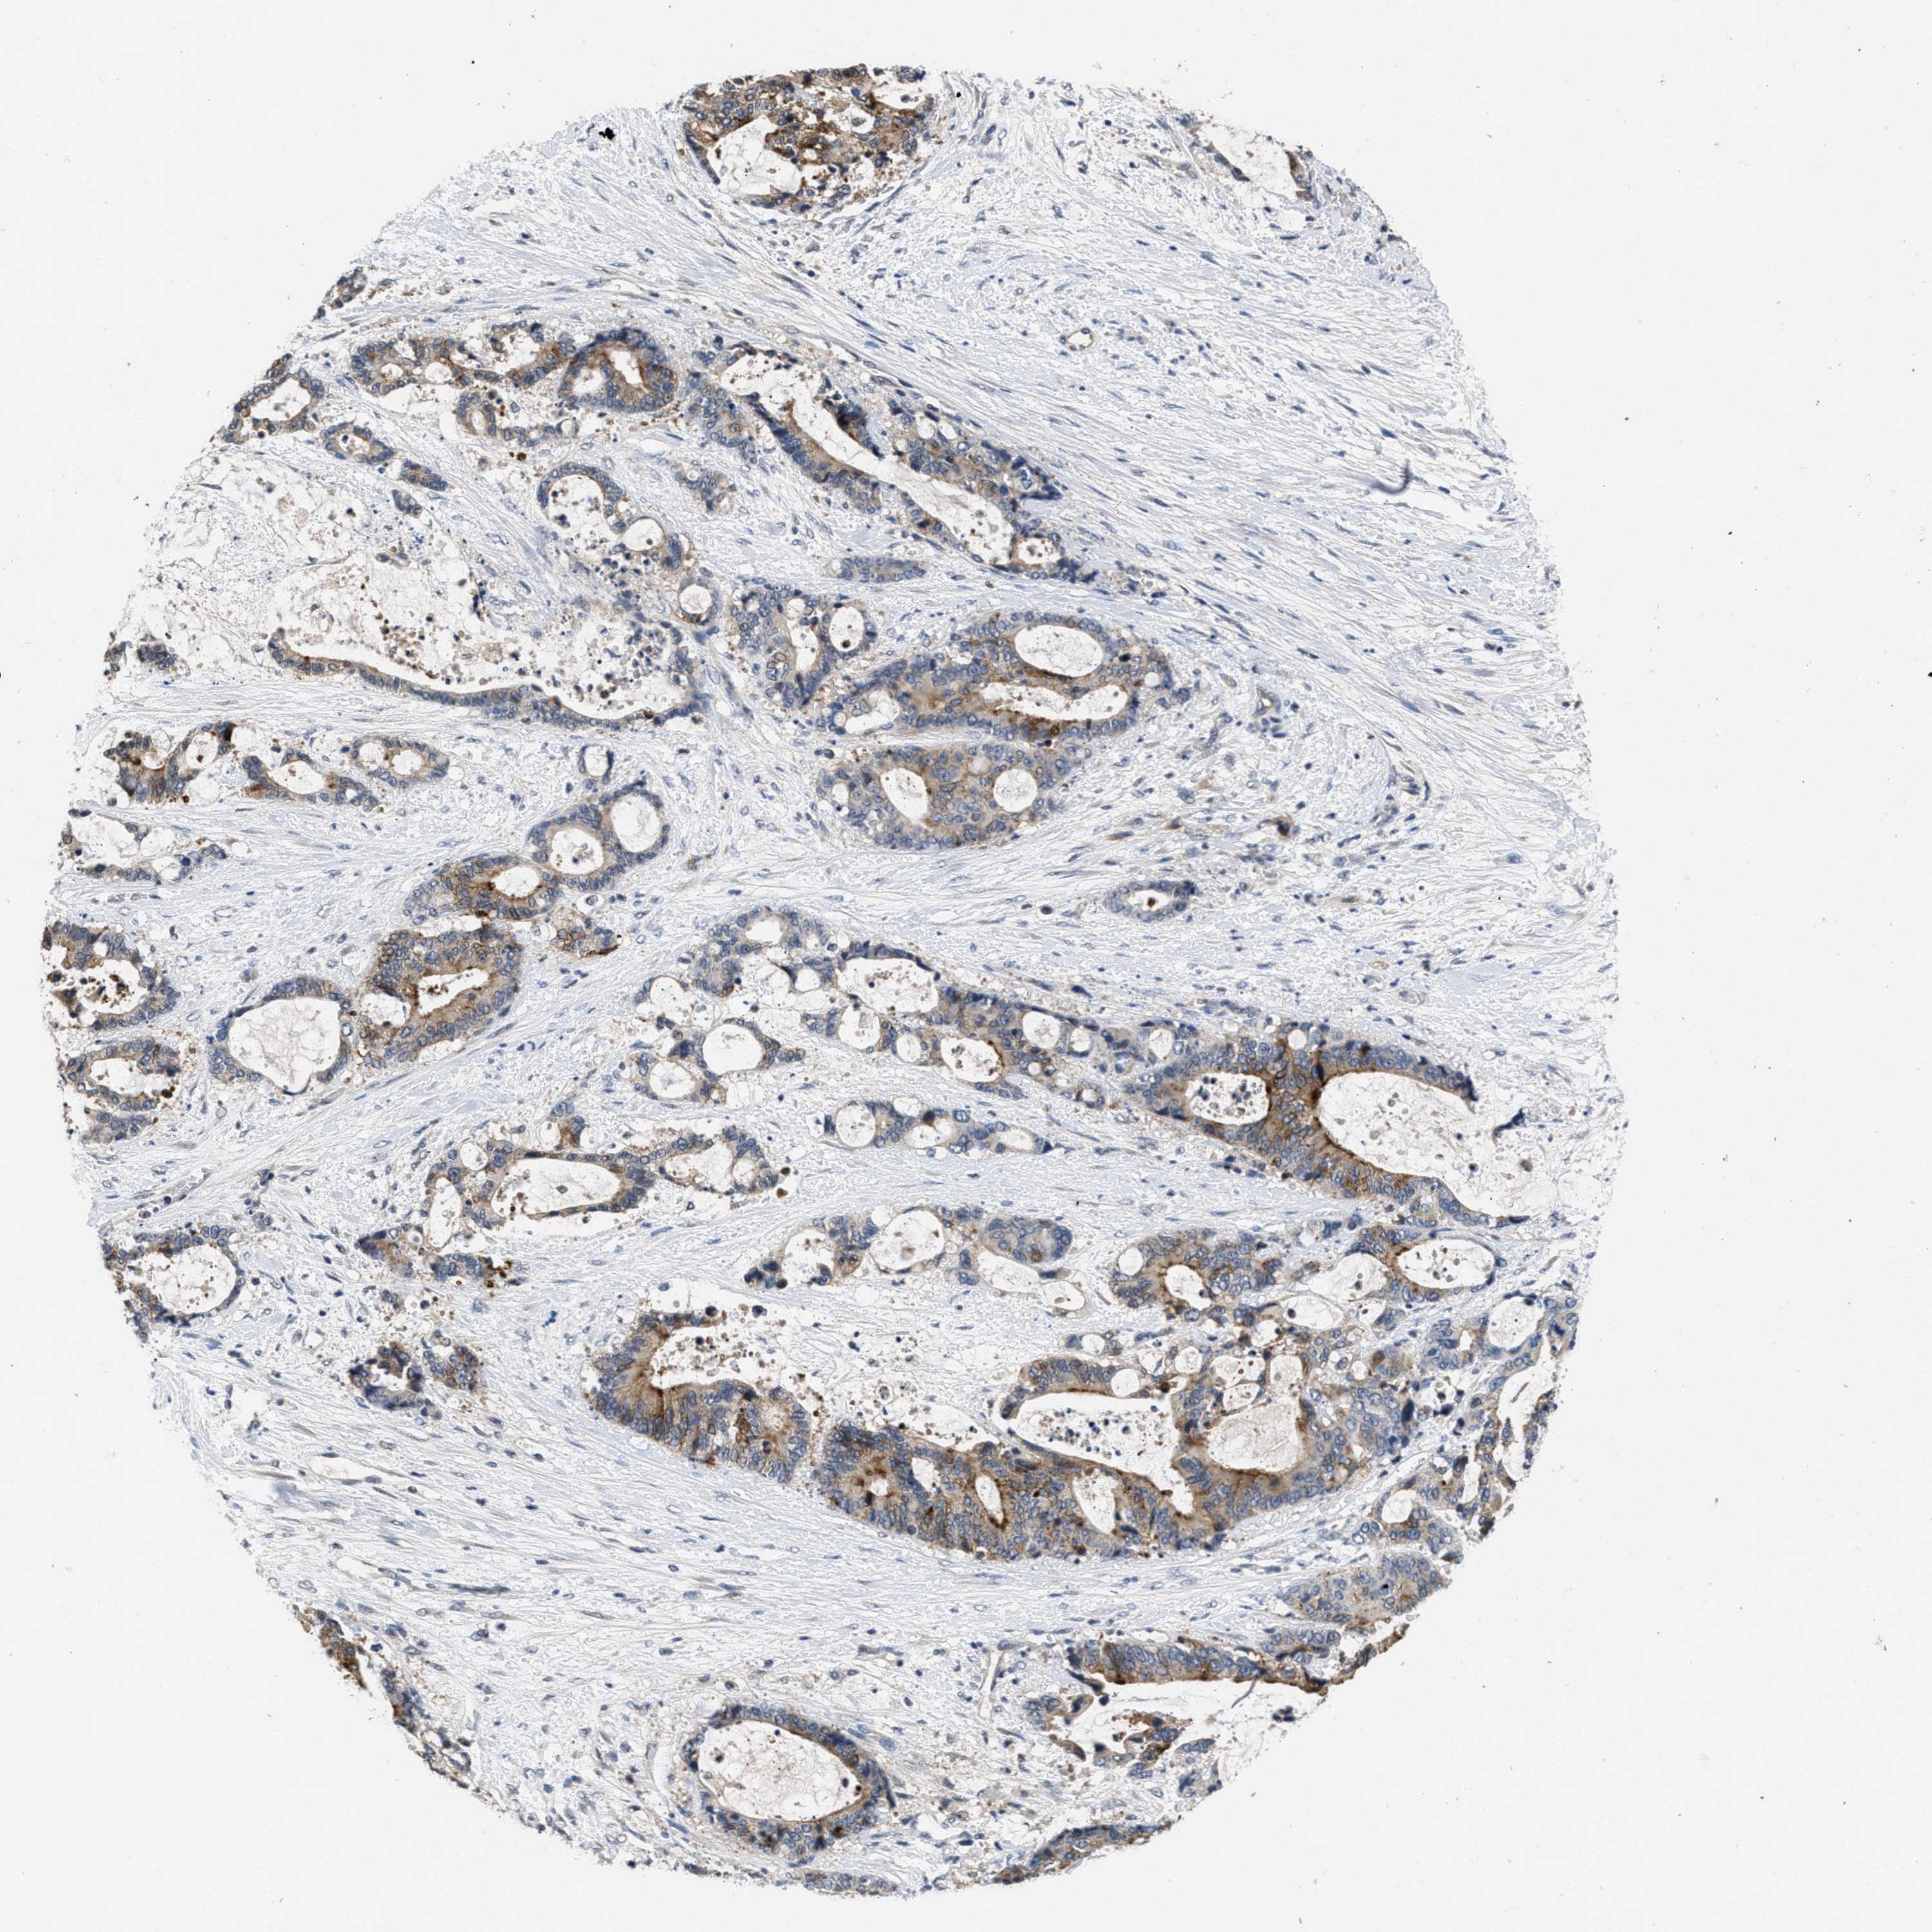

LIVER CANCER - Protein expressioni

A mouse-over function shows sample information and annotation data. Click on an image to view it in a full screen mode. Samples can be filtered based on level of antibody staining by selecting one or several of the following categories: high, medium, low and not detected. The assay and annotation is described here.

Note that samples used for immunohistochemistry by the Human Protein Atlas do not correspond to samples in the TCGA dataset.

Antibody stainingi

Antibody staining in the annotated cell types in the current human tissue is reported as not detected, low, medium, or high, based on conventional immunohistochemistry profiling in selected tissues. This score is based on the combination of the staining intensity and fraction of stained cells.

Each image is clickable and will lead to virtual microscopy that enables deeper exploration of all samples and also displays staining intensity scores, fraction scores and subcellular localization as well as patient and tissue information for each sample.

Antibody HPA018793

Antibody HPA018816

Antibody CAB017815

Staining

High

Medium

Low

Not detected

Intensity

Strong

Moderate

Weak

Negative

Quantity

>75%

75%-25%

<25%

None

Location

Nuclear

Cytoplasmic/membranous

Cytoplasmic/membranous,nuclear

Carcinoma, Hepatocellular, NOS

Cholangiocarcinoma